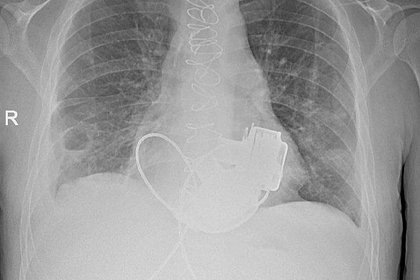

πŸ’€πŸ˜± Π‘Π΅Π·ΠΏΡƒΠ»ΡŒΡΠΎΠ²Ρ‹ΠΉ ΠΏΠ°Ρ†ΠΈΠ΅Π½Ρ‚ Π²Ρ‹ΠΏΠΈΡˆΡƒΡ‚ Π΄ΠΎΠΌΠΎΠΉ Π§Π΅Π»ΠΎΠ²Π΅ΠΊ ΠΈΠ· России выписан ΠΈΠ· Π±ΠΎΠ»ΡŒΠ½ΠΈΡ†Ρ‹ Π±Π΅Π· ΠΊΠ°ΠΊΠΎΠΉ-Π»ΠΈΠ±ΠΎ Ρ‚Π΅Ρ€Π°ΠΏΠΈΠΈ. πŸ”— ΠŸΠΎΠ΄Ρ€ΠΎΠ±Π½Π΅Π΅ ⏰ 20 января 02:04